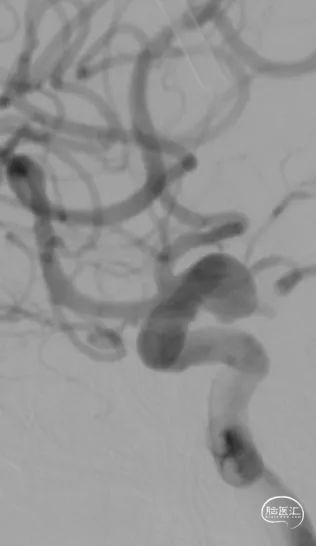

DSA结果:左侧P2段动脉瘤,约1mm*0.8 mm,颈宽约0.8mm,形态不规则。

术前影像DSA、DSA 3D

该病例为左侧大脑后动脉P2段微小宽颈动脉瘤,动脉瘤体直径仅0.9mm,载瘤动脉近端血管直径约1.7mm,远端血管直径约1.1mm,且双侧椎动脉均扭曲明显,但左侧后交通动脉粗大,考虑通过左侧后交通动脉为治疗路径,路途遥远,后交通的成角使得微导丝、微导管的操控存在一定难度;由于动脉瘤体小,因此微导管顺利进入动脉瘤腔内并保证安全是手术的关健点;支架微导管系统成功超选进入P3段远端也是手术成功的关键,对于支架的输送性和贴壁性要求极高。